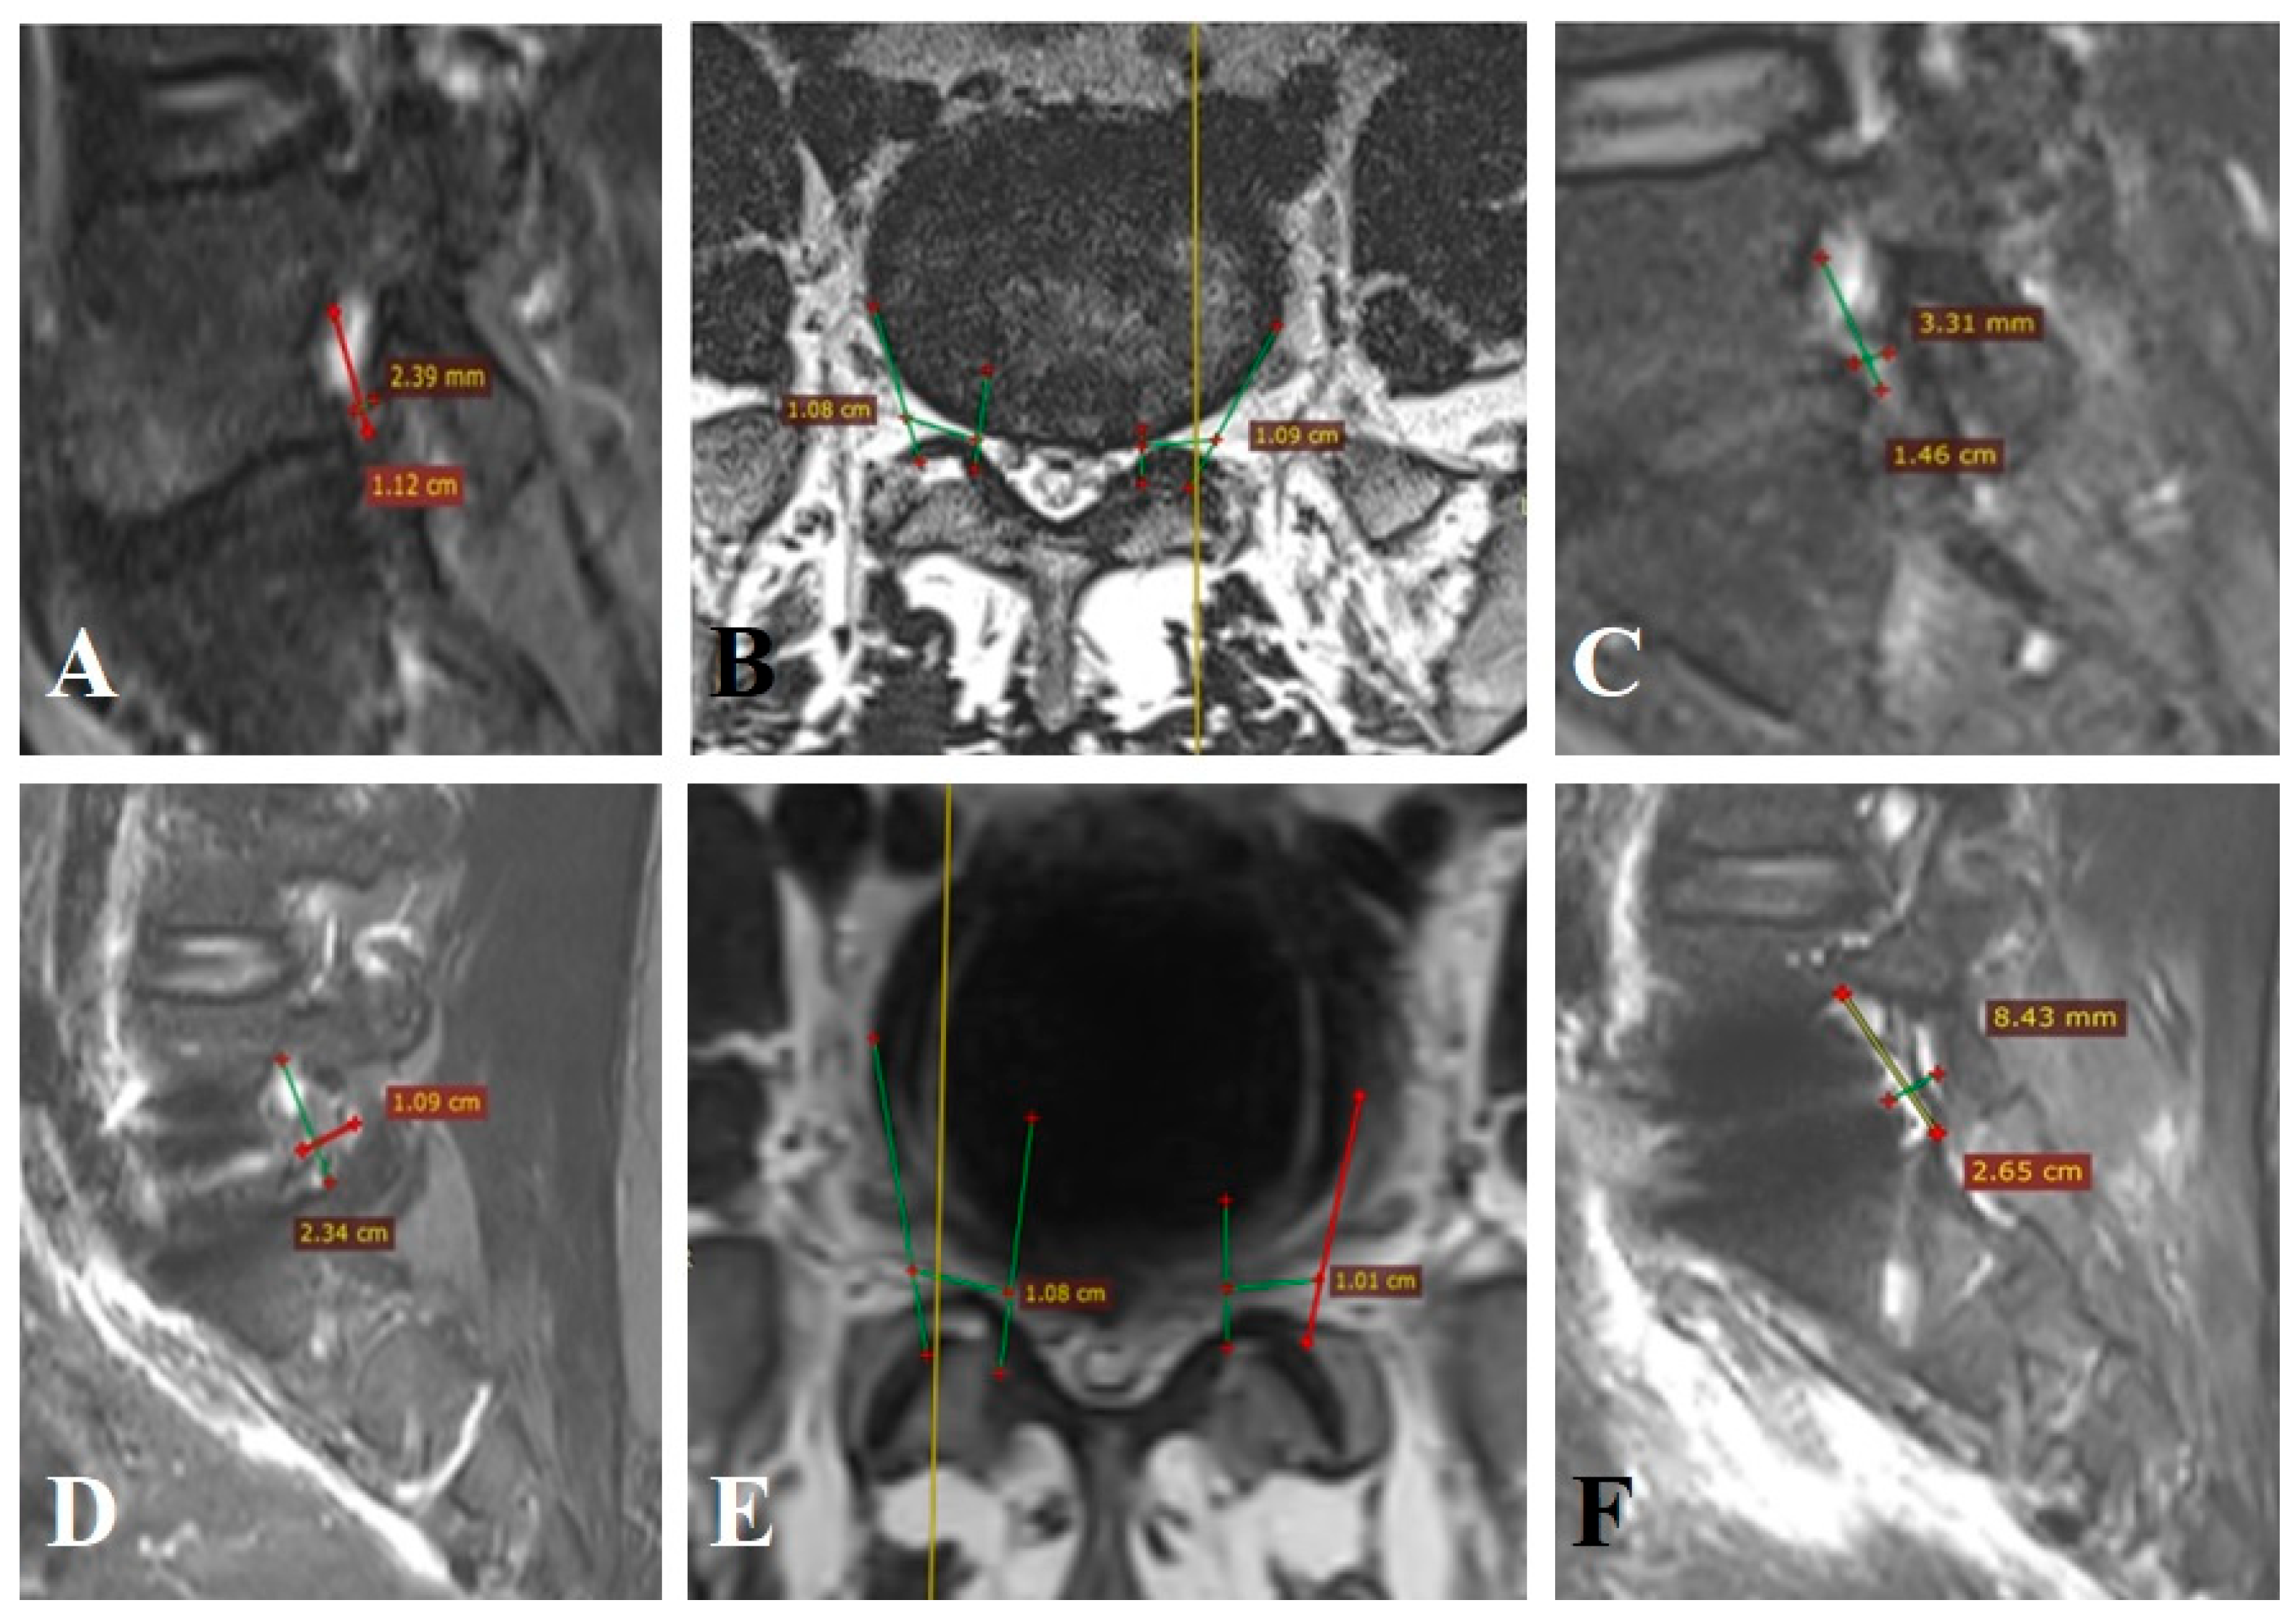

Patient n° 3 is a 35-year-old male, presented with episodic severe lumbar pain radiating to the left lower limb along the L5–S1 dermatome. Pain had persisted for more than three months despite conservative therapy. VAS was 8 cm in the leg and 5 cm in the back, and ODI was 54. MRI showed bilateral foraminal stenosis with moderate degenerative changes: Pfirrmann Grade I–II discs and Fujiwara Grade I–II facet joints. Clinical instability was 5 points per White–Panjabi. On MRI, FC volume at L5–S1 on the left was 412.3 mm3 with nerve volume of 297.1 mm3 (occupancy: 72.1%) (Figure A3A–C). On the right, FC volume was 227.8 mm3 with a nerve volume of 218.2 mm3 (occupancy: 95.7%) (Figure A3A,B). The patient underwent a preperitoneal approach with disc resection and total disc arthroplasty at L5–S1 (ALIF). Postoperatively, indirect bilateral foraminal decompression was achieved. Right FC volume increased to 2003.6 mm3 (occupancy: 10.9%) (Figure A3D,E), a 79.4% increase. Left FC volume increased to 1764.8 mm3 (occupancy: 16.8%) (Figure A3E,F), a 76.6% increase. VAS scores improved to 2 cm (back) and 1 cm (leg). ODI at 12 months was 17.

Figure A3.

MRI of patient n° 3.